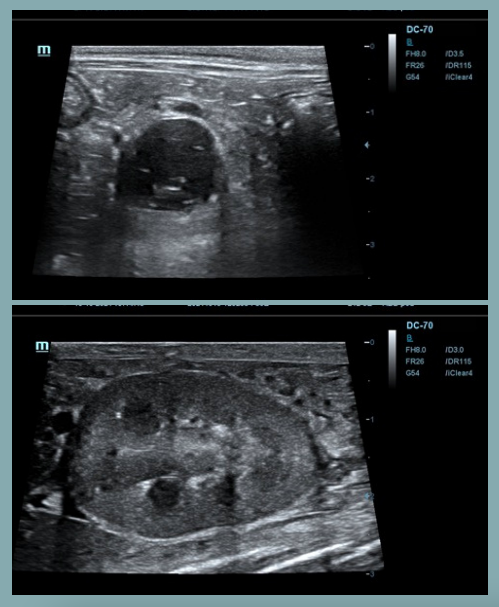

Artefactos: Sombra de borde

- Se forma en los bordes de estructuras curvas o redondeadas, como un quiste, un vaso sanguíneo o una lesión nodular.

- La imagen muestra una sombra longitudinal a cada lado del borde de la estructura redondeada, debido a la refracción de las ondas en el borde estructural.

Artefactos: Refuerzo posterior

- Las ondas sonoras pasan a través de un tejido de baja densidad (fluido) y presentan una mayor intensidad respecto a otras ondas en el mismo plano de profundidad.